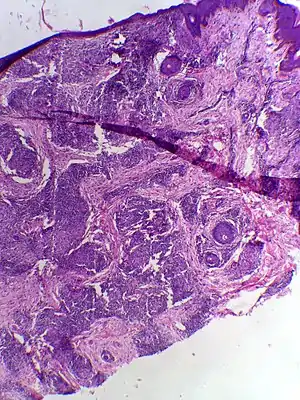

| Skin biopsy in tuberculoid leprosy showing multiple peri-appendageal granulomas. | |

Tuberculoid leprosy is a form of leprosy characterized by solitary skin lesions that are asymmetrically distributed with few lesions and well demarcated edges. There is also early and marked nerve damage. It tends to heal spontaneously.[1]: 345 Tuberculoid leprosy is characterized by the formation of epithelioid cell granulomas with a large number of epithelioid cells. In this form of leprosy Mycobacterium leprae are either absent from the lesion or occur in very small numbers. This type of leprosy is the most benign and the least contagious.[2][3]